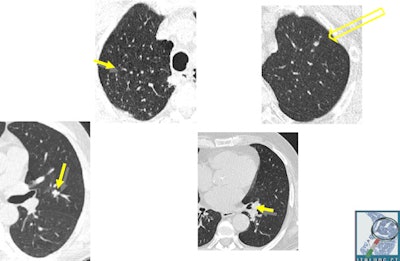

Initial aspects of malignant lesions in the ITALUNG study: squamous adenocarcinomas. Image courtesy of Drs. Mario Mascalchi, Fabio Falaschi, and Giulia Picozzi.Adding to the literature